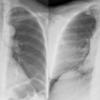

PA vs AP

Ex 1

Date: 03/23/2004

Views: 4726